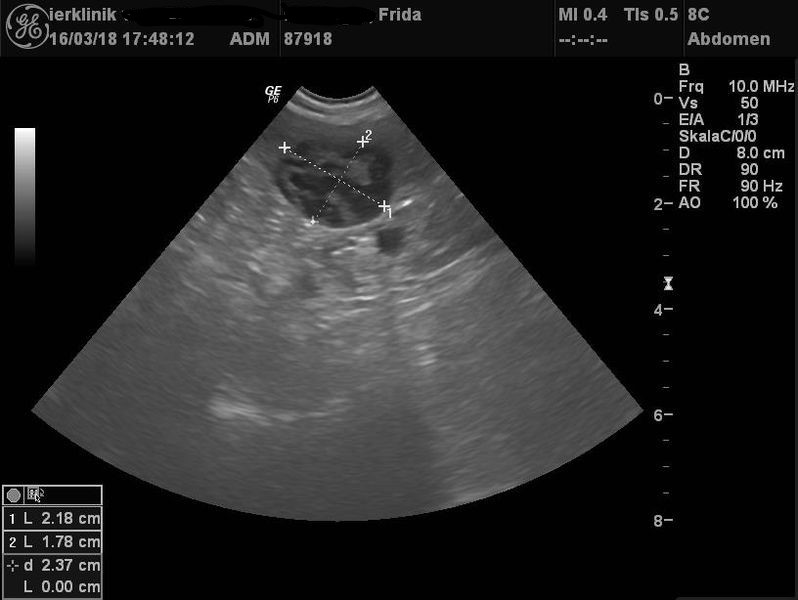

Anfang 2017 ging es Frida dann richtig schlecht. Sie wurde in einer Klinik zur Ultraschalluntersuchung vorgestellt. Das Ergebnis war niederschmetternd: Tumoren an Leber und Milz. Und dies auch noch in einem Umfang, dass die Klinik gleich zur Euthanasie geraten hat. Zu Fridas Glück wollten ihre Besitzer dies aber nicht und haben sich mit ihrem Haustierarzt, Dr. Schabel, in Verbindung gesetzt.

Der intensive Aufwand hat sich bisher mehr als gelohnt: Frida ist fit wie ein Turnschuh. Die sonographische Kontrolluntersuchung drei Monate nach Diagnosestellung zeigten auch eine Verkleinerung des Milztumors um rund ein Viertel. Wir sind alle glücklich, dass unser Sonnenscheinchen nun schon seit zwei Jahren nach Euthanasieempfehlung ein glückliches und gutes Hundeleben führt.